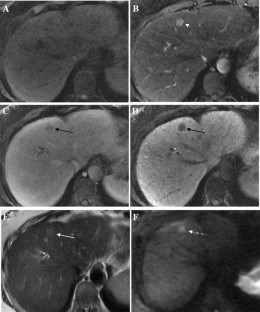

Fig. 1